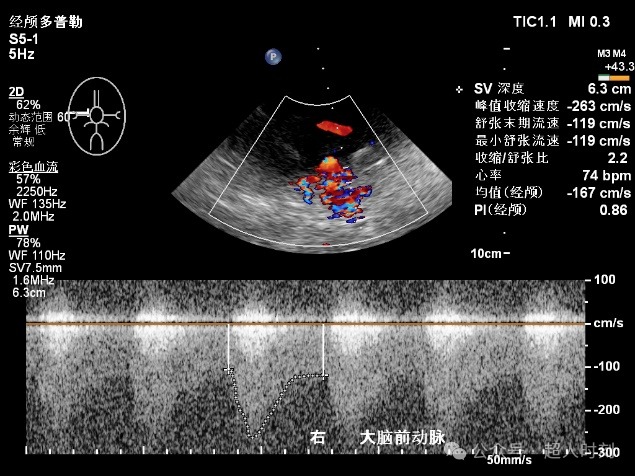

图5c 右大脑后动脉狭窄

图5d 右大脑后动脉血流增快频谱(VP:140cm/s)